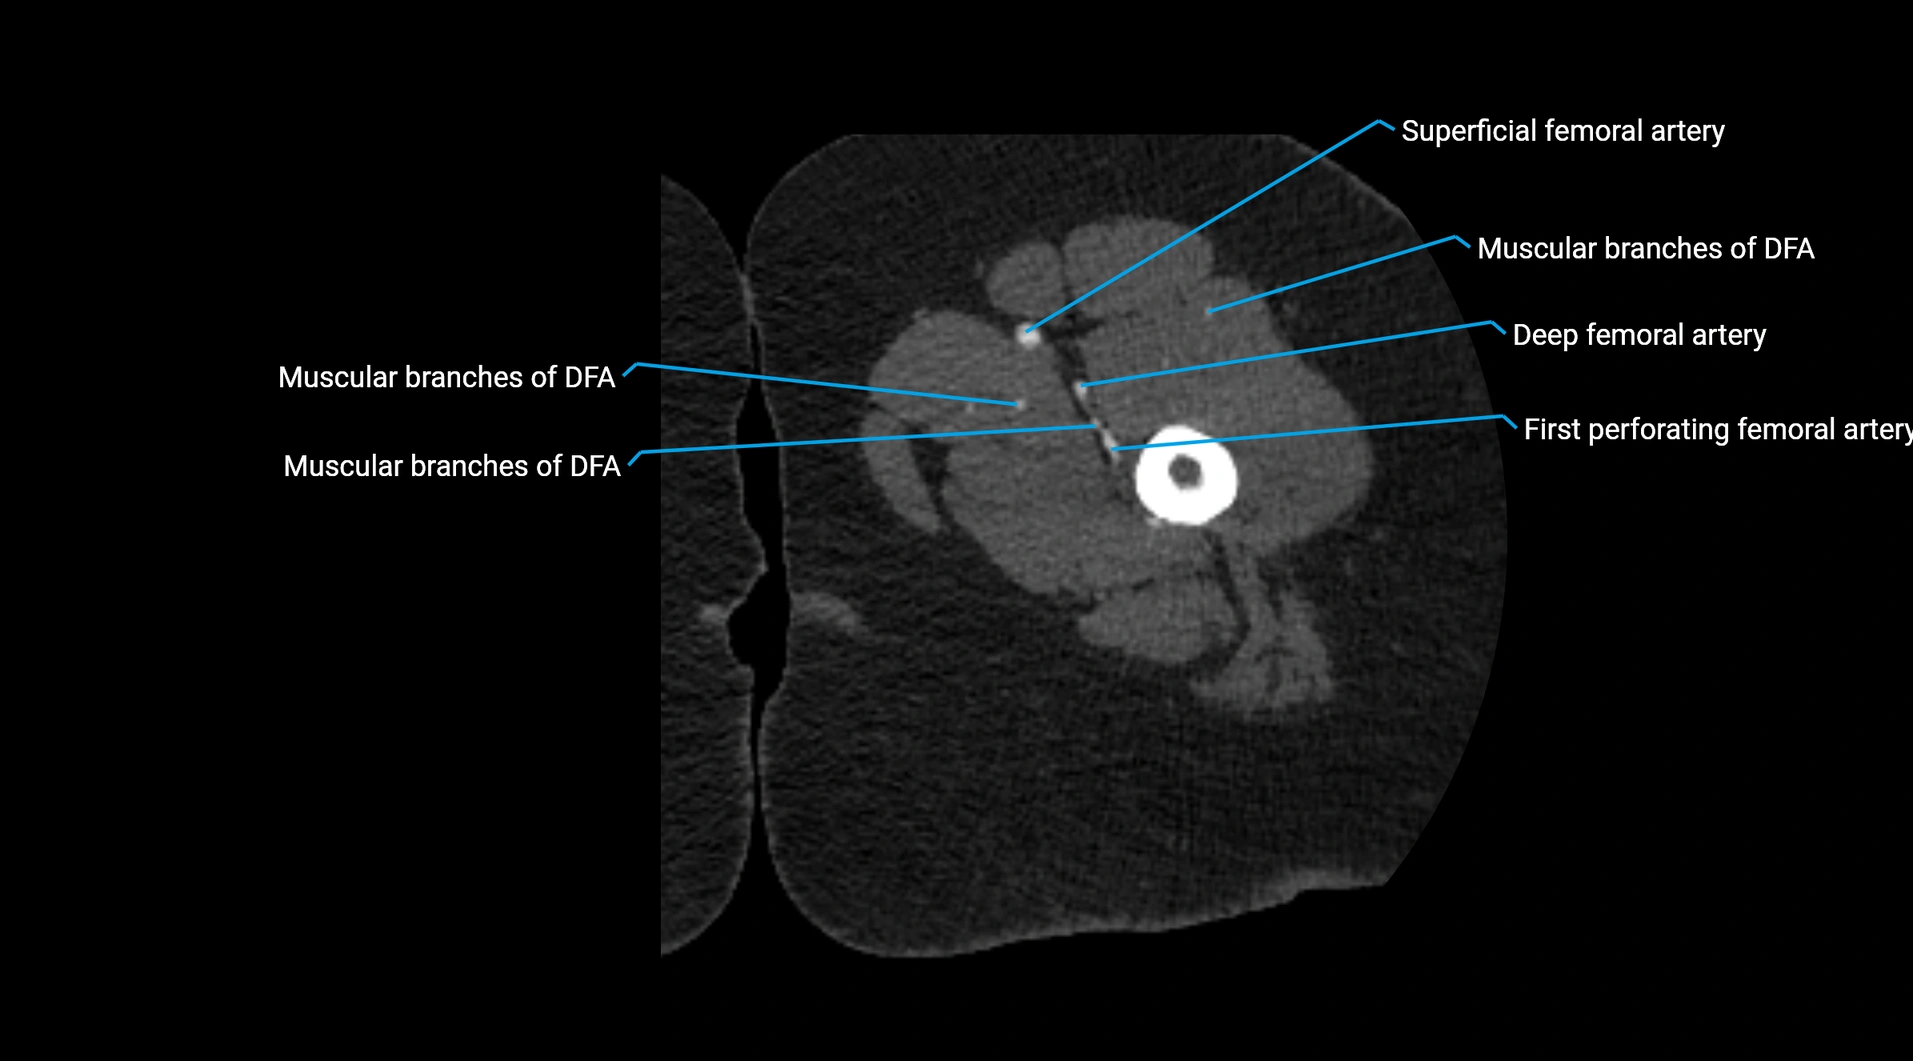

CT images

image

Contrast-enhanced CT (CTA):

• Gold standard for abdominal aortic imaging

• Provides excellent detail of lumen, wall, aneurysm, thrombus, and branch vessels

• Multiplanar and 3D reconstructions help in aneurysm measurement, stent graft planning, and dissection evaluation